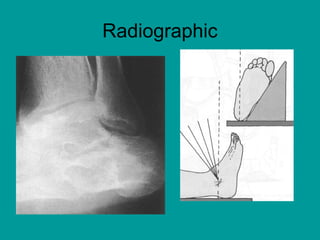

Imaging

• Radiographic views (anteroposterior [AP],

lateral, Harris views)

• Computed tomography (CT) has become

routine to fully delineate the extent of

fractures.CT is especially useful to the

surgeon planning operative intervention.

Plain radiographs alone fail to identify the

degree of fracture extension in almost half

of cases

Radiographic

Computed tomography (CT)